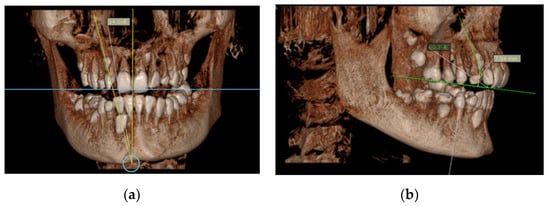

- Horizontal position of the canine cusp tip; the canine was observed to overlap with adjacent teeth using sagittal or coronal CBCT scans. It was assigned according to Ericson and Kurol [17] (sector 1: canine overlapping by up to half the width of the lateral incisor; sector 2: canine overlapping by over half the width of the lateral incisor; sector 3: canine completely overlapping with the lateral incisor; sector 4: canine overlapping by up to half the width of the central incisor; sector 5: canine overlapping over the midline of the maxilla) (Figure 1b);

Figure 1. (a) Occlusal reference arch–location of impacted maxillary canines in axial plane; (b) horizontal position of canine cusp tip: the canine overlap with adjacent teeth in coronal plane (right maxillary impacted canine in sector 2 ad left maxillary impacted canine in sector 4).Figure 1. (a) Occlusal reference arch–location of impacted maxillary canines in axial plane; (b) horizontal position of canine cusp tip: the canine overlap with adjacent teeth in coronal plane (right maxillary impacted canine in sector 2 ad left maxillary impacted canine in sector 4).